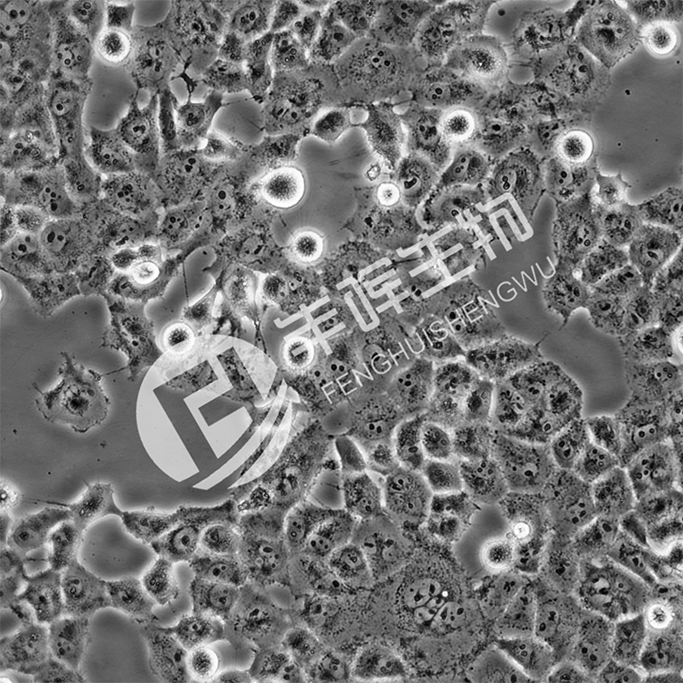

BON-1细胞;人胰腺神经内分泌瘤细胞_

• 细胞种属:人源

• 生长特性:贴壁

• 培养基:DMEM